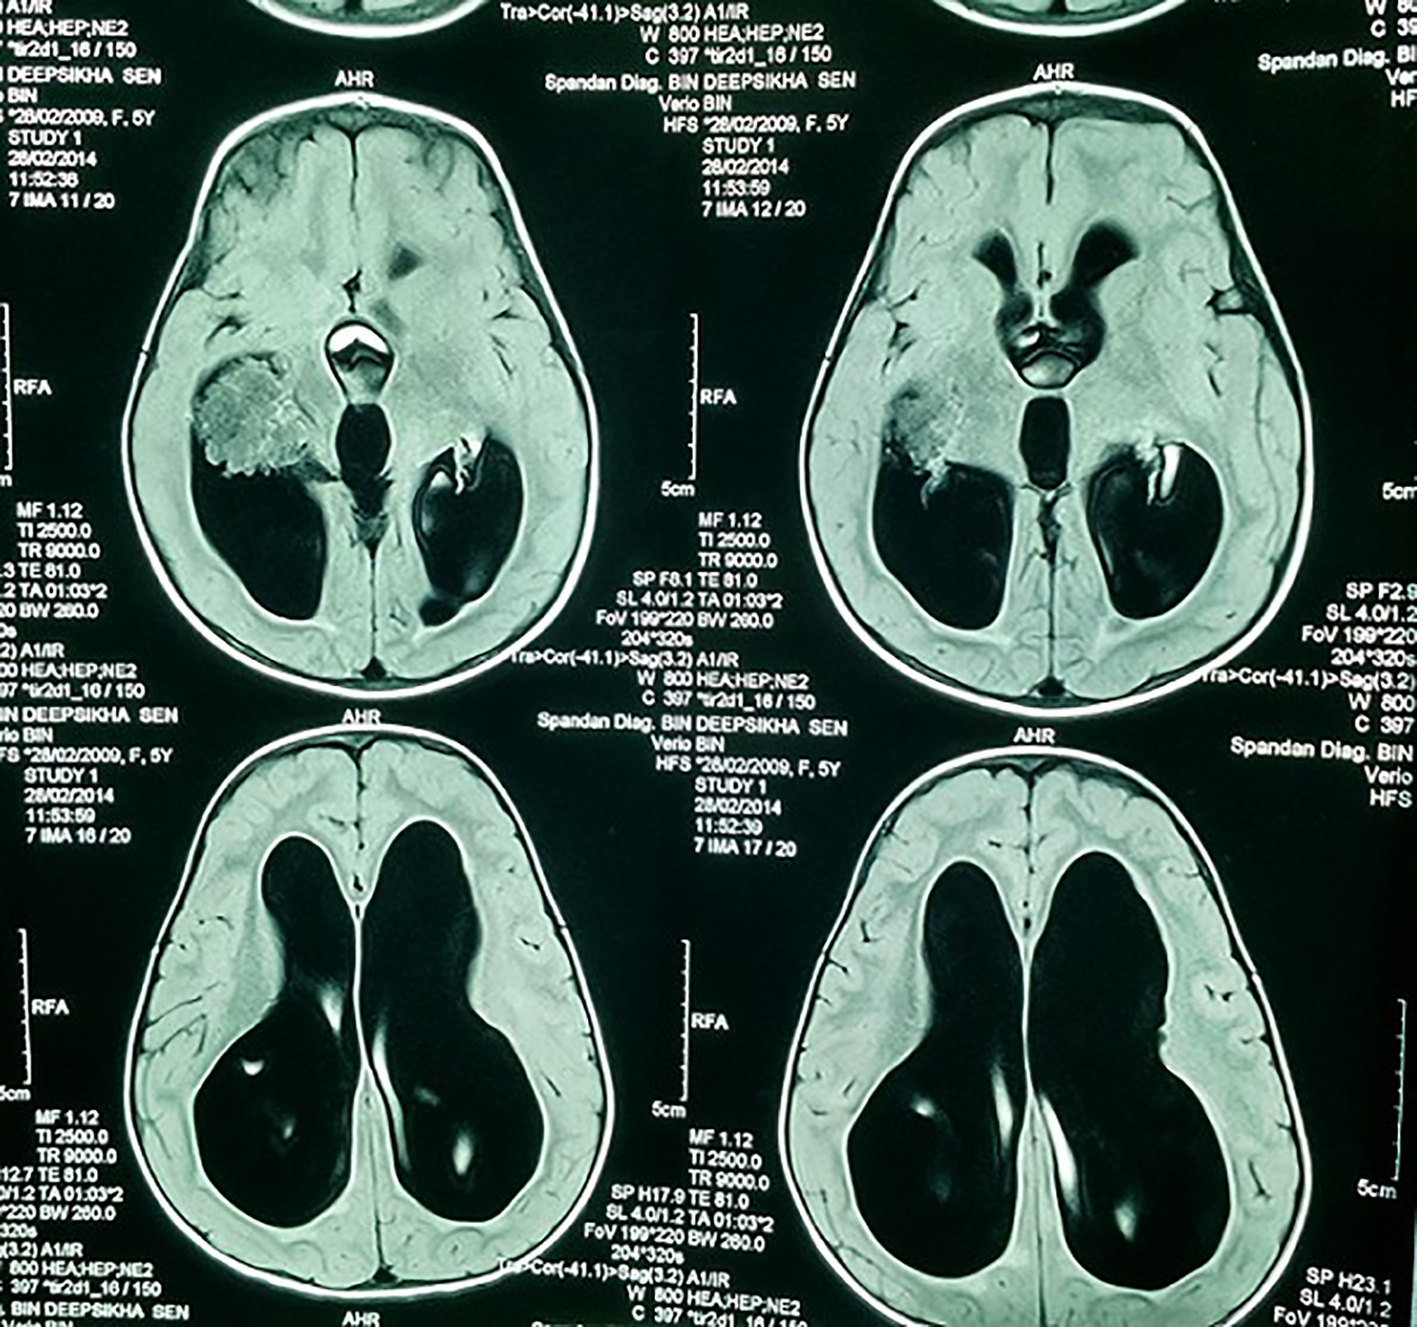

A 7-year-old girl presented with progressive head enlargement since birth, features of raised intracranial pressure in the form of headache, vomiting, excessive crying and excessive drowsiness. Her visual acuity was reduced due to secondary optic atrophy. She had no history of any seizures since birth. Magnetic resonance imaging (MRI) revealed a large hypointense lobulated mass (T2 and FLAIR) originating from the choroid plexus in the temporal horn of the right lateral ventricle measuring almost 50 × 45 × 40 mm in size. All supratentorial ventricles were dilated and the mass was causing compression over adjoining midbrain (Figs. 1-3). With a provisional diagnosis of a choroid plexus mass, the patient was taken up for surgery. A ventriculo-peritoneal shunt was placed for the drainage of excessively forming CSF 2 days prior to the surgery. A right temporal craniotomy was performed and the temporal horn was opened through mid temporal sulcus and the mass was reached. It was a firm friable and vascular mass arising from the choroid plexus on the temporal horn. The tumor had its vascular supply from the anterior choroidal artery.

![]() Click for large image | Figure 3. MRI showing lobulated mass and the dilated ventricles. |